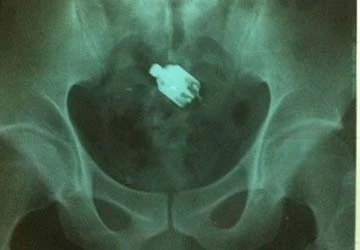

Sau khi rụt rè trình bày lại với bác sĩ về sự cố khi đang “hành sự” với máy dung (loại đồ chơi tình dục dành cho phụ nữ), bệnh nhân này được đưa đi chụp X - quang và nội soi. Hình ảnh siêu âm cho thấy dị vật nằm sâu trong trực tràng, cách cửa hậu môn đến khoảng 30cm. Các bác sĩ quyết định can thiệp để lấy dị vật ra.

Hình ảnh dị vật nằm sâu trong trực tràng trên phim chụp X - quang. Ảnh: H.Hải